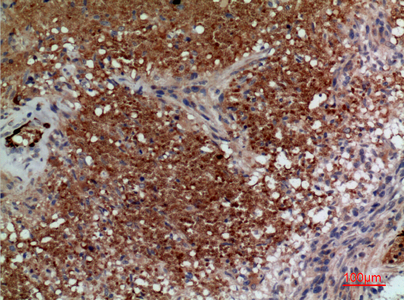

TD-P232253.jpg

Immunohistochemistry analysis of paraffin-embedded Human brain using CD241 antibody.High-pressure and temperature Sodium Citrate pH 6.0 was used for antigen retrieval.